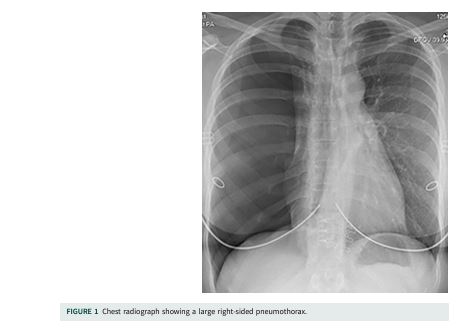

Her chest radiograph (CXR) on presentation showed a large right-sided pneumothorax (figure 1). She had a normal pulse, blood pressure, respiratory rate and oxygen saturations on air at rest. However, simple exertion such as walking a few steps made her very breathless. As per established local guidance, she was offered the choice between conservative management, admission with chest drain insertion or ambulatory management with either a 12 French gauge (FG) Seldinger chest drain (which would be connected to an ambulatory bag) or an 8FG Rocket Pleural Vent. Northumbria Healthcare NHS Trust has a well-established ambulatory pneumothorax service [1]. The ambulatory devices are inserted by Accident and Emergency Department practitioners and the subsequent management takes place on the Medical Ambulatory Care unit by acute medicine physicians, with the respiratory team getting involved in case of complications or non-resolution. With the premise that this was a primary pneumothorax (as the patient had no apparent lung disease), and because the priority of the patient was admission avoidance, she was seen by the pleural team and ambulatory management was initiated with an 8FG Rocket Pleural Vent.